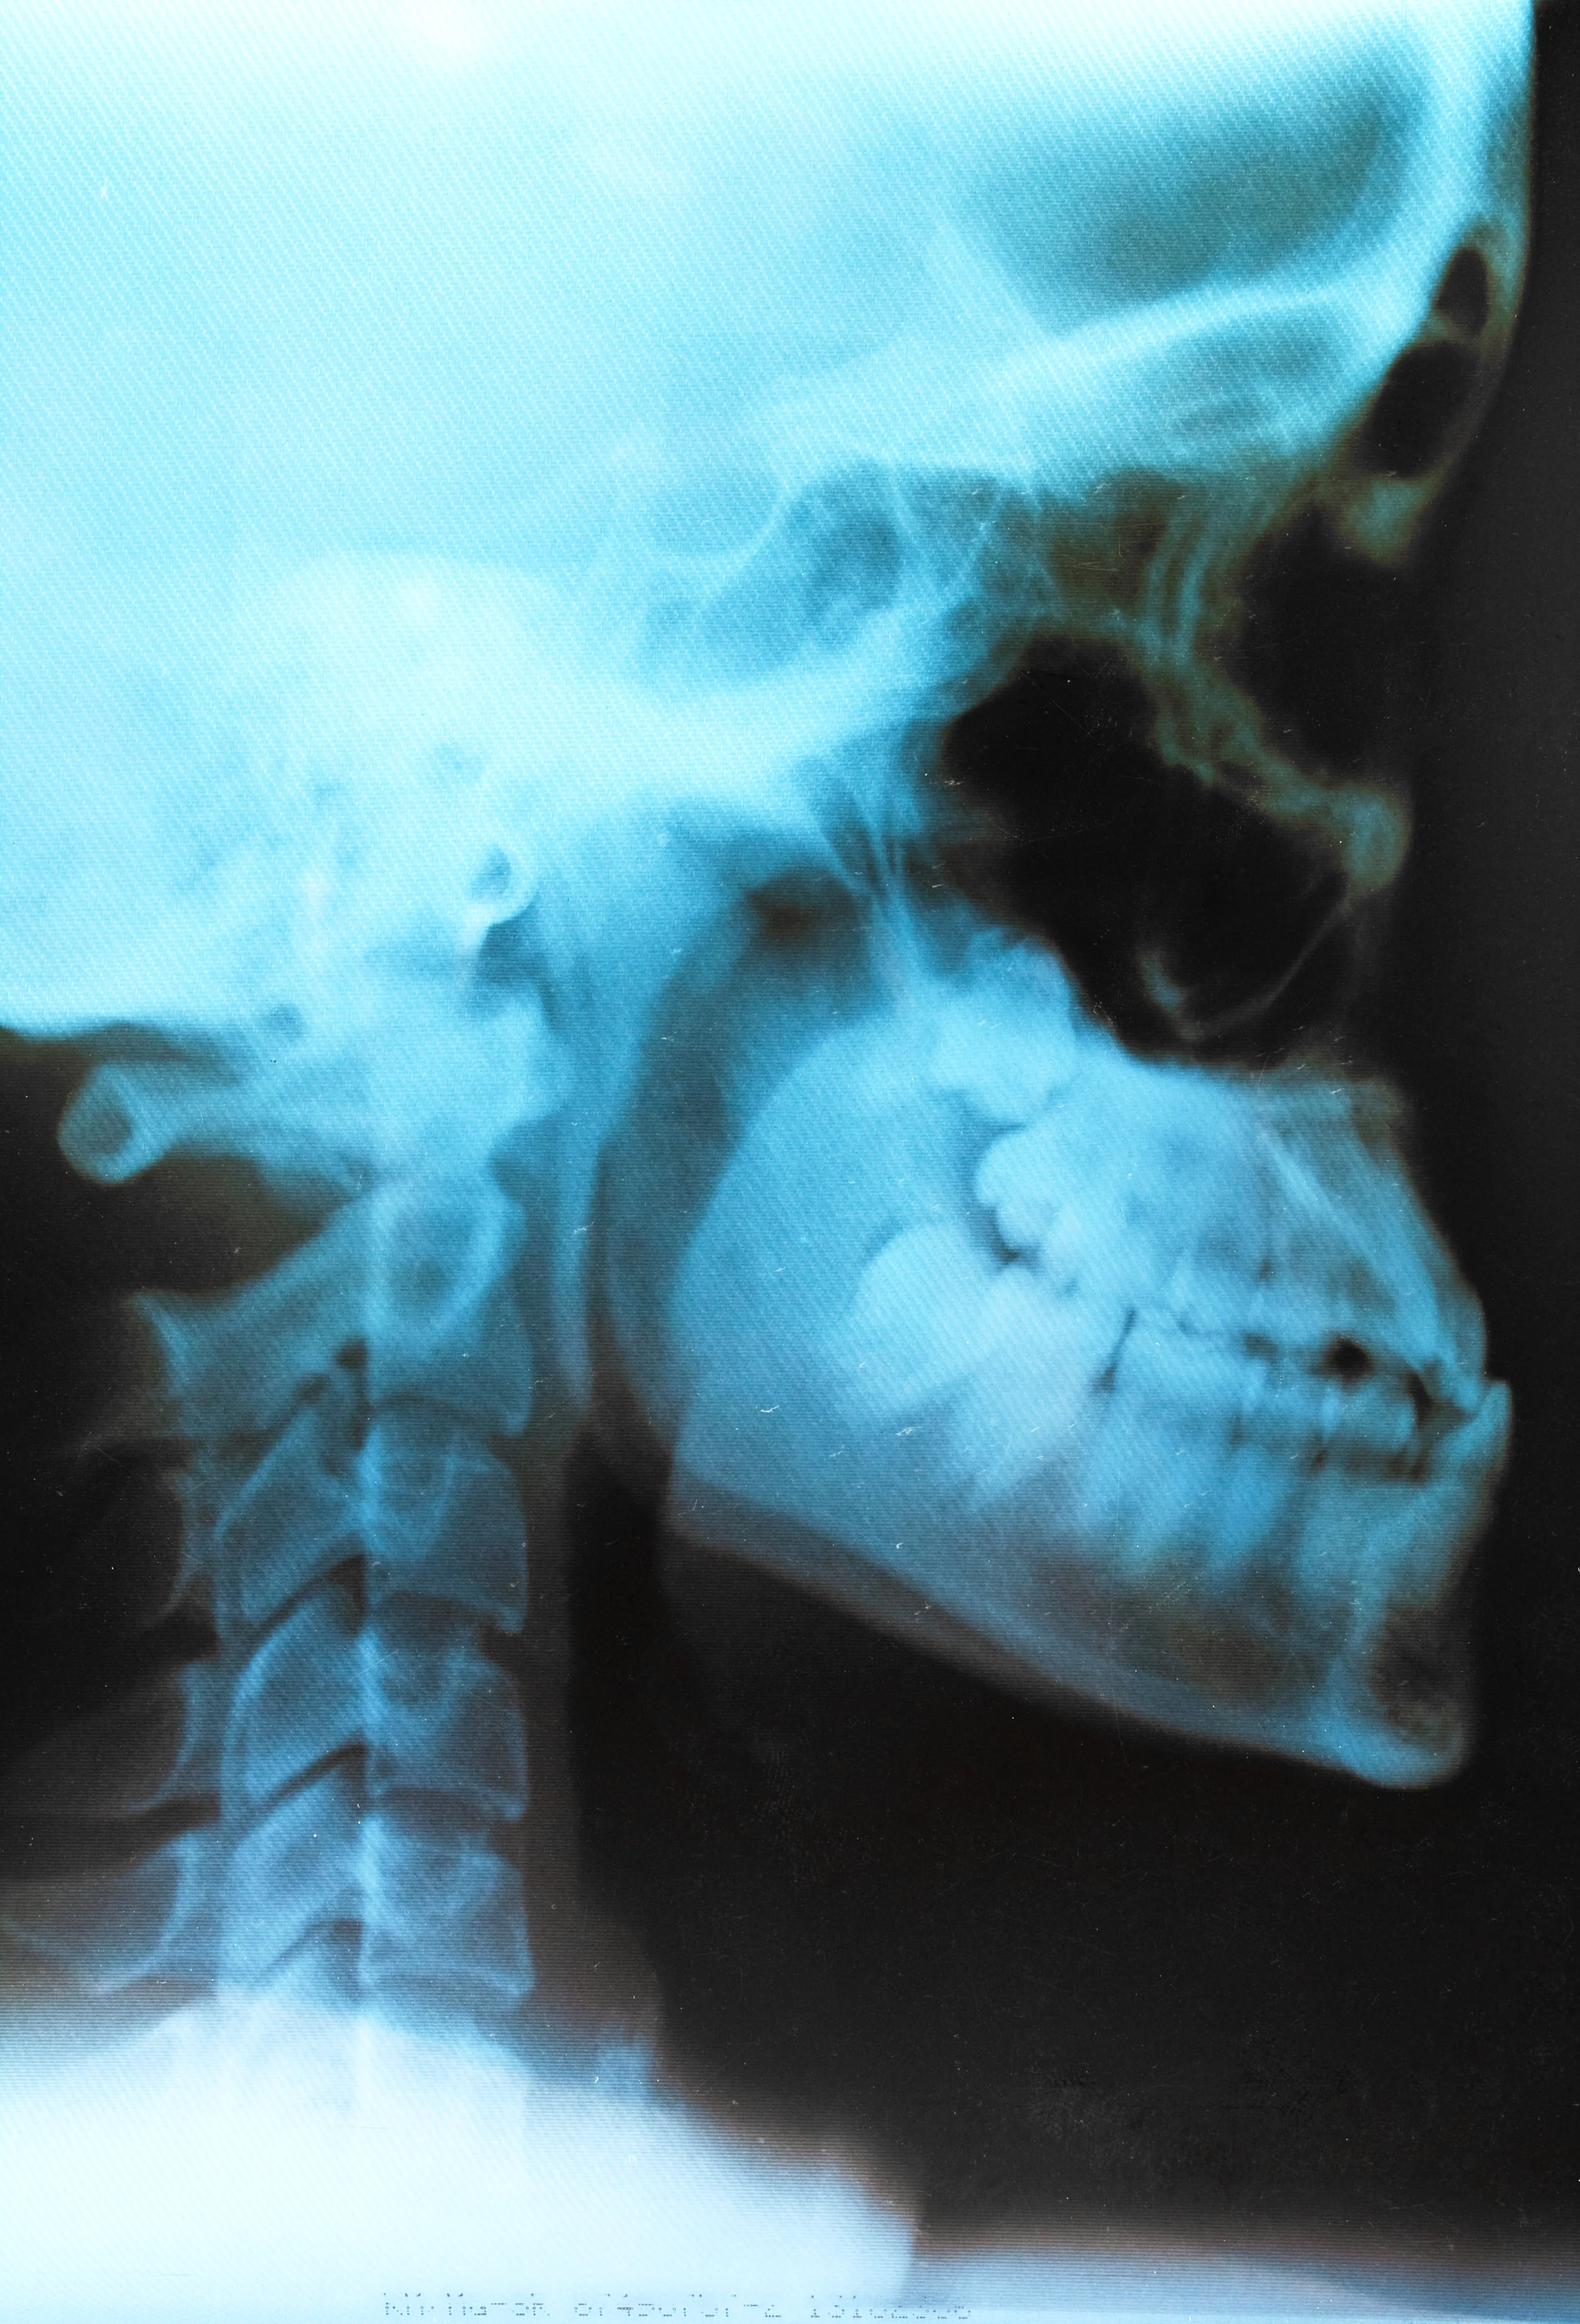

Effectuer une radiographie :

Les médecins pratiquant l’ostéopathie exigent une radiographie des cervicales avant d’intervenir sur le patient. « Cette dernière permet d’éliminer une pathologie osseuse, malformative, voire neurologique », explique ainsi le Dr . Norbert Teisseire. Chez les ostéopathes non-médecins, cet examen n’est pas demandé de façon systématique. Michel Sala estime, néanmoins, qu’elle est « obligatoire en cas de traumatisme ».